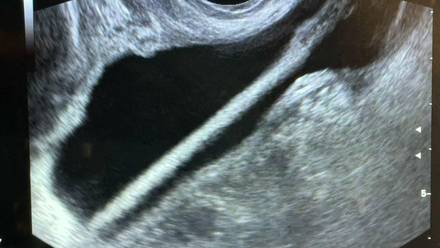

Фото: Министерство здравоохранения Московской области

Врачи Красногорской больницы спасли 46-летнюю пациентку, достав из ее мочевого пузыря косметический карандаш. Об этом в среду, 11 февраля, сообщила пресс-служба Министерства здравоохранения Московской области.

Как сообщил заведующий урологическим отделением Красногорской больницы Петр Сысоев, женщине сделали УЗИ, после этого провели операцию, в ходе которой удалили карандаш с помощью эндоскопа.

— Все прошло успешно, без каких-либо осложнений, — сказал врач.

В ведомстве уточнили, что пациентку уже выписали домой. В региональном Минздраве также добавили, что подобные действия очень опасны, поскольку могут привести к травмам и инфекциям. Медики призвали не экспериментировать с собственным организмом.